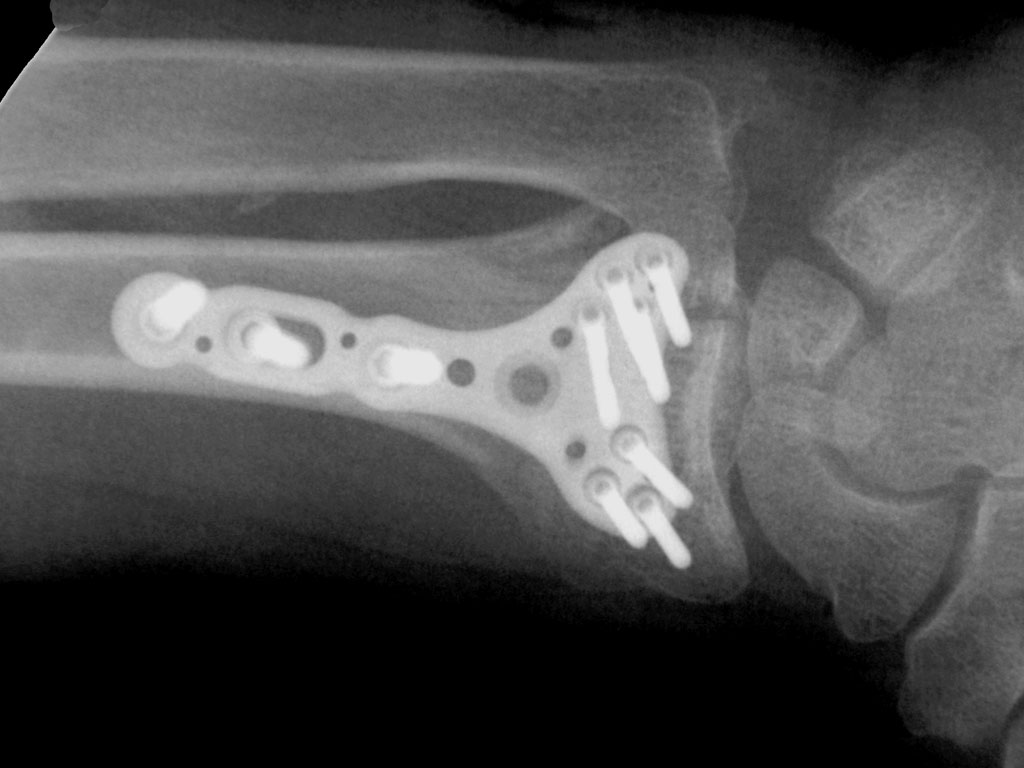

Case Study: Fixation Of a Distal Radius Fracture

Patient History: This is an 85 year-old, right hand dominant female who sustained a ground level fall on an outstretched hand. She sustained a Frykman IV, Melone class I closed distal radius fracture that had three intra-articular components. The ulnar column component was split transversely. The Frag-Loc Compression Screw was ideal for this type of fracture that is classified as unstable.